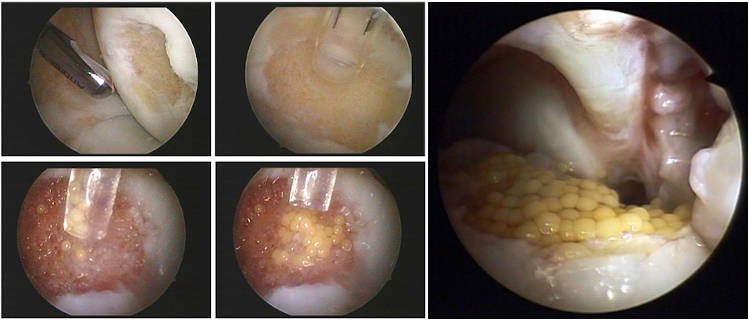

Τεχνική των μικροκαταγμάτων όπου με ειδικό εργαλείο δημιουργούνται μικρές οπές στο σημείο της βλάβης στο υποχόνδριο, ώστε να απελευθερώνεται αίμα πλούσιο σε αναγεννητικούς παράγοντες στο σημείο της βλάβης με αποτέλεσμα προοδευτικά να σχηματίζεται χόνδρος ινώδης στην περιοχή. Ο συγκεκριμένος χόνδρος δεν έχει τις ιδιότητες του υαλοειδούς χόνδρου είναι λιγότερο εύκαμπτος και ελαστικός. Η τεχνική δείνει να είναι αρκετά αποτελεσματική σε βλάβες χόνδρου μέχρι 2 εκατοστά και καλή ποιότητα υποχόνδριου ιστού.

Τον τελευταίο χρόνο, η ομάδα της Β' Ορθοπαιδικής Κλινικής του Ιασώ Θεσσαλίας χρησιμοποιεί την τεχνική Graftnet με εντυπωσιακά αποτελέσματα, όπου στον ίδιο χρόνο συλλέγει υγιή χόνδρο από μη φορτιζόμενη επιφάνεια, τον δυναμοποιεί και ενεργοποιεί ανακατεύοντας τον με αυτόλογους αυξητικούς παράγοντες και τον επανατοποθετεί στη περιοχή της βλάβης όπου θα αναπτυχθεί νέος αρθρικός χόνδρος.